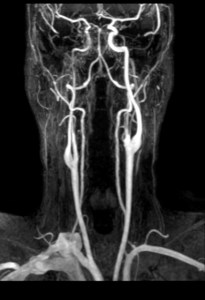

L’angioIRM en temps de vol (3D TOF) sans injection de produit de contraste détecte à la fois la sténose artérielle et l’hématome pariétal en regard.

L’angioIRM des troncs supra-aortiques (TSA) avec injection de produit de contraste complétera le bilan en évaluant le degré et la longueur de la sténose artérielle, la présence d’anévrysme.